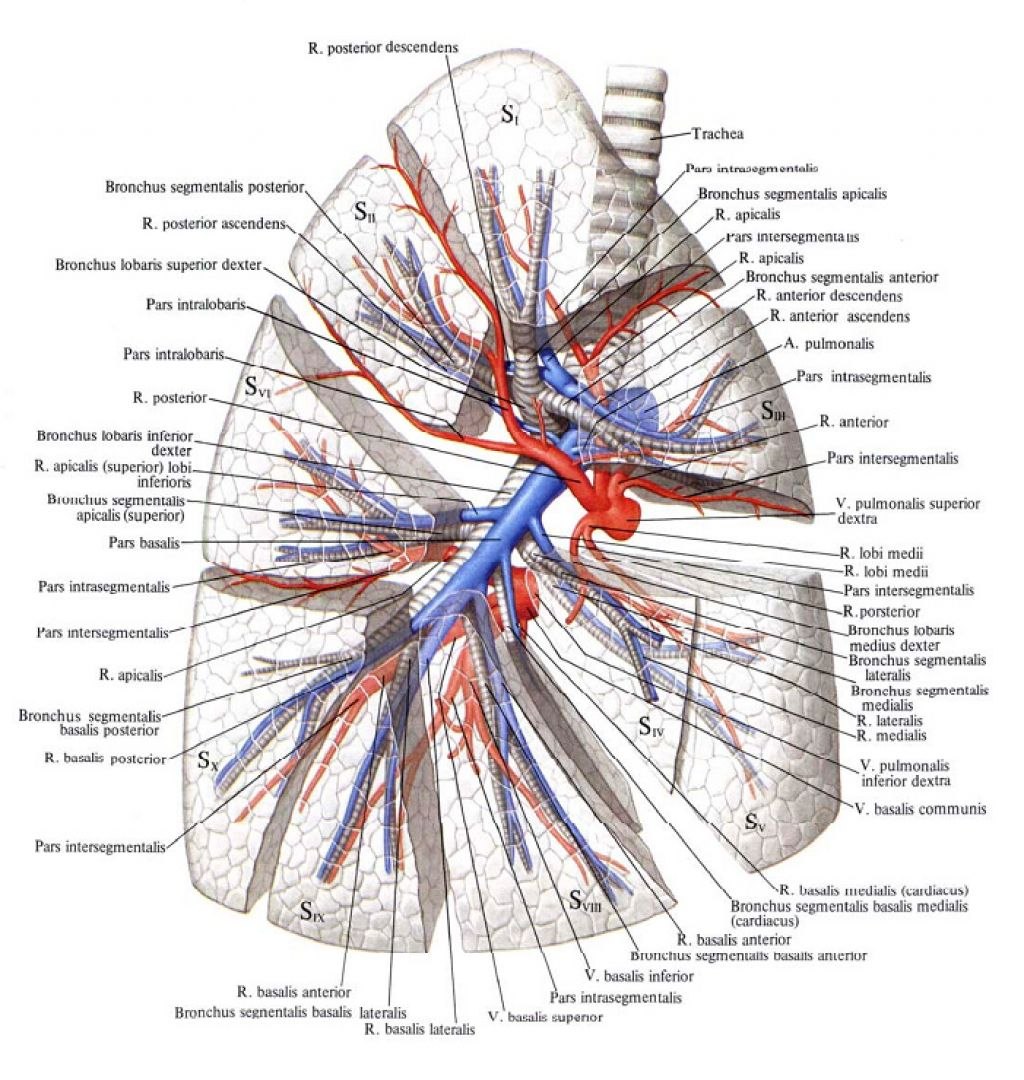

Анатомические изображения сегментов легких различных животных

Раздел: Другие животные